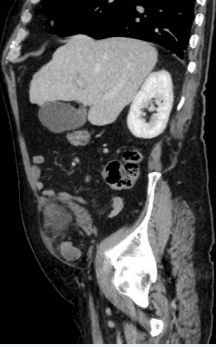

On examination, his vital signs were normal. His abdomen was soft and tender around right lower quadrant. A mass was also palpable at the right lower quadrant. Biochemistry examination revealed mildly raised white cell count (13 x 10* 9/L) and lactate of 2.4mmol/L). The computed tomography (CT) of abdomen/ pelvis demonstrated strangulated small bowel loops within a right SH (Figure 1, 2 and 3).

Figure 3: Right Spigelian hernia containing small bowel loop in sagittal view of CT scan.